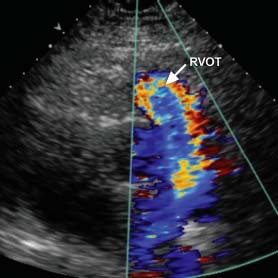

A 40-year-old man with known hypertrophic cardiomyopathy presented with syncope after coughing. Physical examination revealed a systolic murmur that was accentuated by the Valsalva maneuver. An electrocardiogram suggested biventricular hypertrophy and biatrial enlargement (Fig. 1). Echocardiograms revealed asymmetric septal hypertrophy with a diastolic septal thickness of 2.3 cm, and evidence of flow acceleration across the right ventricular outflow tract (RVOT) and left ventricular outflow tract (LVOT) (Figs. 2 and 3).

Fig. 3 Transthoracic echocardiogram (parasternal long-axis view) shows systolic flow acceleration across the right ventricular outflow tract (RVOT).

Real-time motion image is available at www.texasheart.org/journal.